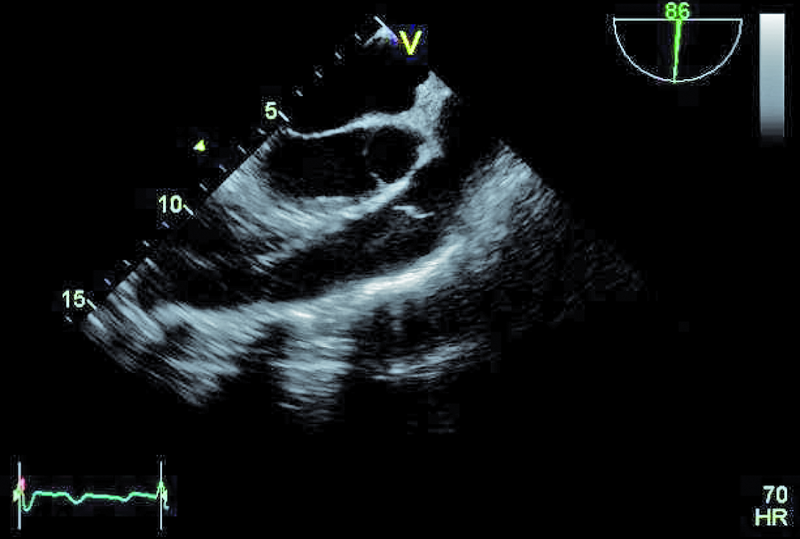

Szczegóły oceny układu krążenia z okresu przeprowadzanych operacji nie były znane. Można było jedynie przypuszczać, że śluzak prawej komory mógł zaburzać funkcję zastawki trójdzielnej, a jego resekcja pozostawiła stopniowo narastającą nieszczelność zastawki. Wymiana zastawki na biologiczną była konieczna, ale spowodowała dalsze problemy u chorego. Degeneracja zastawek biologicznych u osoby młodej może postępować dynamicznie, nawet bez obecności dodatkowych czynników nasilających to zjawisko, jak niewydolność nerek czy nadczynność przytarczyc. Kolejnym czynnikiem, poza wiekiem, wpływającym na odpowiedź immunologiczną, może być samo ujście trójdzielne, w którym procesy wapniowo-fosforanowe w odpowiedzi na rozciąganie płatków są silne. Warto także nadmienić, że zastawki biologiczne stentowe, jak użyta w tym wypadku, charakteryzują się szybszym tempem zwyrodnienia niż zastawki bezstentowe. Rozpoznanie strukturalnego zwyrodnienia bioprotezy w ujściu trójdzielnym nie powinno nastręczać trudności. Wczesnymi objawami procesu jest pogrubienie i usztywnienie płatków, które stają się w obrazie ultradźwiękowym jaśniejsze i nieregularne w zarysie (ryc. 1, 2). Ponieważ proces postępuje, włóknienie i zwapnienia obejmują najpierw spoidła, a następnie całe płatki i pierścień zastawki. W przedstawionym przypadku zwyrodnienie prowadzi zarówno do stenozy, jak i niedomykalności. O stenozie zastawki w ujściu trójdzielnym zawsze należy myśleć, gdy gradient średni napływu przekracza 6 mm Hg (ryc. 3). Niedomykalność trójdzielna uważana jest za istotną, kiedy talia strumienia ma szerokość co najmniej 6 mm (ryc. 4). Warto dodać, że rejestrowane zmiany hemodynamicznie są podobne do tych, jakie obserwuje się w natywnej zastawce trójdzielnej np. w rzadkim uszkodzeniu poreumatycznym. Chory ma wskazania do kolejnej interwencji kardiochirurgicznej i operacja w tym wypadku nie powinna być odkładana, żeby nie doprowadzić do narastającej niewydolności jam prawego serca. By uzupełnić ocenę, zarejestrowano projekcję na drogę odpływu prawej komory (ryc. 5). Wykluczono cechy nadciśnienia płucnego i niedomykalność zastawki płucnej. Zwrócono uwagę na istotnie poszerzone jamę prawego przedsionka i żyłę główną dolną (ryc. 6), odpowiadające nieprawidłowościom w badaniu fizykalnym – hepatomegalii i obrzękom obwodowym. Poza operacją można rozważyć wykonanie zabiegu techniką przezcewnikową i wszczepienie zastawki Edwards SAPIEN lub Melody (valve-in-valve). W tym wypadku na decyzji o leczeniu operacyjnym zaważyły jednak preferencja chorego i doświadczenie ośrodka.